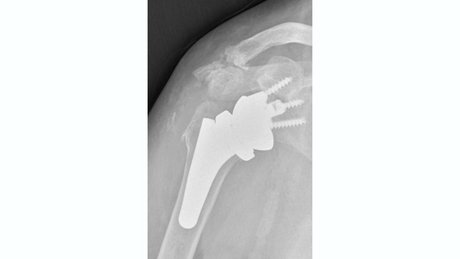

Therapieoption: Implantation einer anatomischen/inversen Schulterprothese

Die Implantation einer Schulterprothese kann bei Arthrose im Schultergelenk, der sogenannten Omarthrose, nötig werden. Hierbei kann man zwei verschiedenen Formen der Arthrose unterscheiden:

In einem Fall ist die Rotatorenmanschette, also die umgebenden Sehnen an der Schulter, welche die Stabilität und Beweglichkeit des Gelenkes gewährleisten, intakt. Der Knorpel ist jedoch aufgebraucht. Bei der Implantation einer Prothese werden die Gelenkpartner ersetzt und deren Form wird beibehalten. Eine sogenannte anatomische Schulterprothese wird implantiert.

Sollte die Rotatorenmanschette, also die umgebenden Sehnen an der Schulter, welche die Stabilität und Beweglichkeit des Gelenkes gewährleisten, nicht mehr intakt sein, dann ist ein anderer Prothesentyp nötig. Hierbei ist die Prothese so aufgebaut, dass sie durch Umkehr der Gelenkformen, die Funktion der fehlenden Sehnen übernimmt. Die flache Pfanne wird sphärisch und der ursprünglich runde Kopf wird als Schale implantiert. Dadurch kann man trotz fehlender Rotatorenmanschette die nötige Stabilität und Beweglichkeit des Schultergelenkes wiederherstellen. Eine sogenannte inverse Schulterprothese wird implantiert.

Sollte bei Ihnen eine Prothesenimplantation durchgeführt werden, sind unter Umständen zuvor verschiedenen bildgebende Verfahren nötig um die korrekte Prothese auswählen zu können.

Bei allen Prothesenformen gibt es verschiedenen Designs. Insgesamt versucht man so knochensparend wie möglich zu operieren. Das bedeutet viel vom eigenen Knochen zu erhalten. Schaftlose Prothesen und kurze Schäfte werden daher bevorzugt. Bei vorbestehender eingeschränkter Knochenqualität kann zur Aufrechterhaltung der Stabilität eine etwas längere Verankerung im Knochen notwendig sein.

Insgesamt ist wichtig, dass man individuell entscheiden muss ob eine Prothese implantiert wird und welche Form der Prothese gewählt wird.

Üblicherweise schließt sich an die Operation eine 5-6 wöchige Nachbehandlung ohne Kraftaufwendung am Arm an. Im Anschluss ist die Prothese gut eingeheilt und man kann mit einer Belastungssteigerung starten. Dies erfolgt üblicherweise im Rahmen eine Rehabilitation, welche bei der Festlegung des Operationstermins, vorab reserviert werden kann.

Auch Revision einer vorhandenen Schulterprothese, die Konversion von anatomischer Prothese auf eine inverse Prothese, partieller Wechsel oder gesamter Wechsel werden angeboten und durchgeführt.